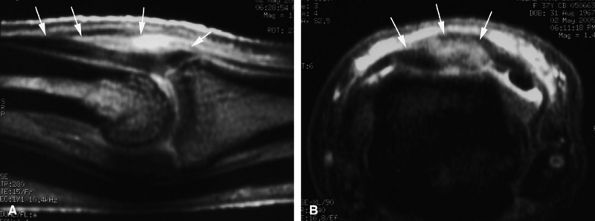

FIGURE 11.2 ● Metacarpophalangeal joints. (A) T1-weighted coronal image. (B) T1-weighted axial image. The proper collateral ligament (PCL) is lax in extension and shows heterogeneous signal intensity on coronal and axial images. ACL, accessory collateral ligament; VP, volar plate; LM, lumbrical; DIO, dorsal interosseous; PIO, palmar interosseous; MC, metacarpal; RSB, radial sagittal band; EDC, extensor digitorum communis; EIT, extensor indicis proprius tendon; FDS, flexor digitorum superficialis tendon; FDP, flexor digitorum profundus tendon; A1, A1 annular pulley.